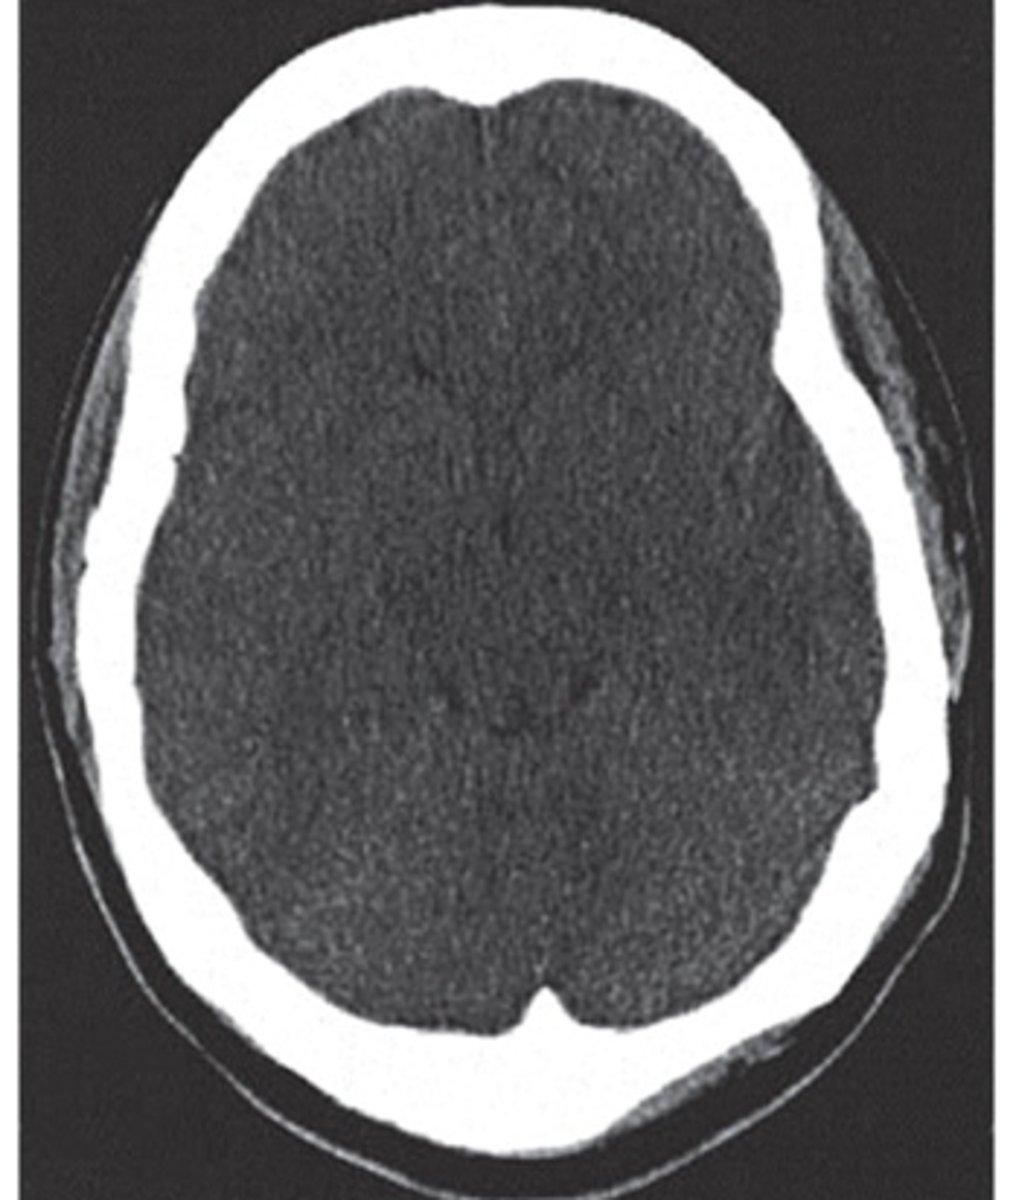

CT interpretation

denser tissue is brighter (hyperdense)

less dense is darker (hypodense)

bone is white, air is black

brain window- structures to be identified and differentiated

bone window- best for visualizing bone